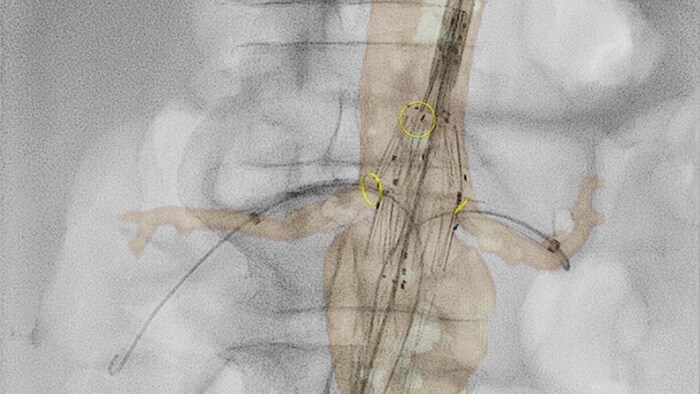

Fiber Optic RealShape technology

This unique innovation, available to you exclusively from Philips, enables real-time, 3D visualization of devices* inside the body using the wonders of light.